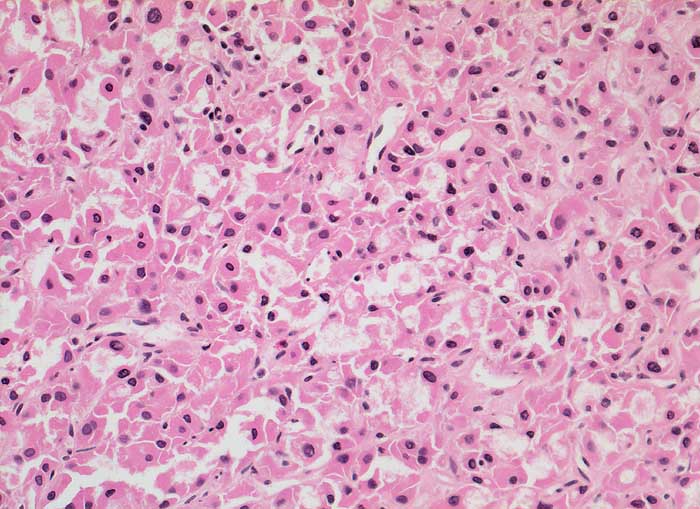

Ausgeprägte Kernpolymorphie, Nukleolenatypie und unscharfe Zytoplasmagrenzen der oxyphilen Zellen sind Malignitätszeichen. Eine Unterscheidung von onkozytären Adenomen und Karzinomen ist zytologisch aber nicht sicher möglich.

Gezeigt werden zwei Fälle von histologisch gesicherten onkozytären Karzinomen.